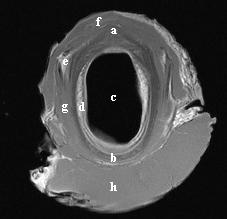

| dc.description.abstract | A study was performed to establish the appearance of normal equine laryngeal cartilages using magnetic resonance imaging. Specimens were acquired from clinically normal horses that were euthanized for reasons other than respiratory disease. Three in situ and 5 ex vivo larynges were imaged using a 0.3 Tesla system. Images were obtained in the transverse plane using T1-weighted 3D spin echo, T2-weighted 3D spin echo, T2-weighted gradient echo, short tau inversion recovery (STIR), and proton density spin echo sequences. Five ex vivo larynges were also imaged in the transverse plane using a 1.5 Tesla system, sequences included T1-weighted 3D spin echo, T2-weighted 3D turbo-spin echo, turbo inversion recovery (TIRM), and proton density spin echo sequences. A frozen gross laryngeal specimen was sliced in 5-mm transverse sections for comparison to the MR images. Excellent correlation was found between MR images and the gross transverse sections. Successful imaging was accomplished using both imaging systems; however, the 1.5 Tesla system yielded superior image resolution. The 0.3 Tesla imaging system would accommodate the intact equine head, which was not possible using the 1.5 Tesla MRI system. The internal morphology of the laryngeal cartilages was clearly identified in all imaging sequences obtained. Cartilages were found to differ in signal intensity based on the tissue composition and imaging sequences performed. MRI was determined to be a useful imaging modality for evaluating the cartilage morphology of the equine larynx. Further investigation is required to document pathologic morphology. | en |